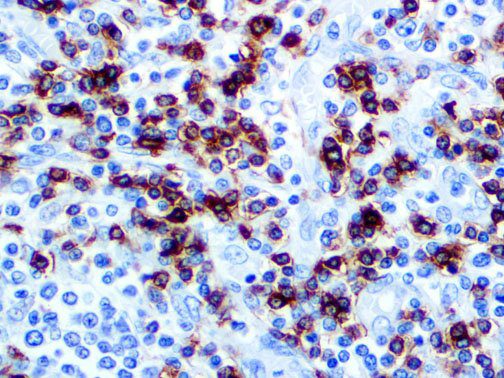

The first cytokines released are interleukin 1β (IL-1β) and tumor necrosis factor-α (TNF-α), which attract a variety of circulating white blood cells (WBCs) to the infection site, including neutrophils, monocytes, macrophages, and natural killer (NK) cells. This response, along with the antipathogenic chemicals released by these cells (i.e., complement), comprise the innate immune response. These cells directly attack the invading pathogen and also release additional cytokines, chief among them interleukin-1 and 6 (IL-6). IL-6 is essential for invoking the adaptive immune response, which calls T-cells, B-cells, and T helper (Th) cells to the infection site. IL-6 also stimulates further recruitment, proliferation and activation of macrophages.

It is the ICU physician who is most likely to witness one of the deadliest manifestations of the abnormal immunological response, the cytokine storm syndrome (CSS). This response is also referred to by some as the cytokine release syndrome (CRS). CSS is characterized by continuous activation and expansion of macrophage and lymphocyte populations, which secrete large amounts of cytokines, causing the cytokine storm. This massive cytokine release is akin to hemophagocytic lymphohistiocytosis (HLH) disease, a syndrome characterized by initial unchecked and persistent activation of cytotoxic T lymphocytes and NK cells.

This activation induces inflammatory monocytes to highly express IL-6, starting a localized and then systemic cascade effect that results in hyperproduction of IL-6, which accelerates the inflammatory process. Because IL-6 also increases vascular permeability, excessive levels cause blood vessels to become very leaky. This, along with clotting factors released from vascular endothelial cells, stimulates the coagulation cascade, resulting in microthrombosis (tiny clots), which leads to ischemia and tissue death of the kidney, intestines, heart, liver, brain and extremities.